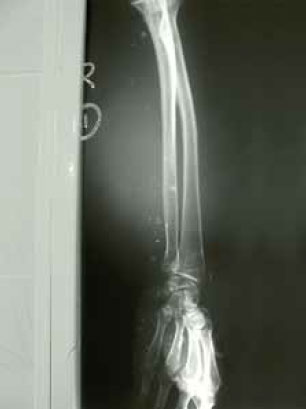

Бризантное действие взрыва может ломать длинные трубчатые кости, а взрывная волна, следующая за ударом, затем сдирает мягкие ткани. Одним из возможных последствий этого для жертвы, находившейся близко к эпицентру взрыва, является травматическая ампутация, которая обычно происходит по верхней трети большеберцовой кости. Наблюдается также выпадение внутренних органов. Часто встречаются обширные раны мышечных тканей.